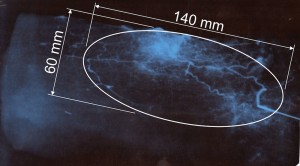

Особенности зоны, кровоснабжаемой из перфорирующей ветви малоберцовой артерии исследовались нами посредством проведения рентгенангиографии на патоморфологическом материале. Были исследованы 16 препаратов лоскутов. Учитывая территорию кровоснабжения исследуемой ангиосомы, которая составляет максимально до 18 см в длину и до 9 см в ширину, кожно-фасциальный лоскут препарировался в несколько больших границах (+ 3 см в длину и ширину), но не выходя за пределы гребня большеберцовой кости [4]. Выделенная перфорантная ветвь малоберцовой артерии зондировалась канюлей на глубину 2-4 см, при затруднении проведения канюли, её проводили по металлическому проводнику 0.014 inch. После этого на артерию поверх канюли накладывался турникет, и герметизировали сосуды по периферии лоскута путем наложения лигатур или методом электрокоагуляции (рис. 2). В ходе подготовки сосудов к контрастированию они промывались раствором гепарина (5 000 Ед / 100 мл). Сосудистое русло заполнялось под давлением йод содержащим контрастным веществом (Ультравист – 370; Визипак – 320), производились рентгенангиографические снимки в нескольких фазах наполнения. С целью определения размеров зоны с устойчивым кровоснабжением от перфорантной артерии (ангиосомы) и её индивидуальной вариабельности, проводили планиметрическое исследование с определением возможных размеров формирования лоскута (рис. 3).

Рис. 2 А. Выделение перфорантной артерии и взятие патоморфологического материала (кожно-фасциального лоскута); Б. Препарат с зондированной перфорантной артерией и проведенной герметизацией.

Рис. 3. А. Рентгенангиографический снимок препарата надлодыжечного лоскута с визуализацией зоны кровоснабжаемой перфорантом до уровня гребня большеберцовой кости. Б. Условная статистически устойчивая зона кровоснабжения препарата кожно-фасциального латерального надлодыжечного лоскута.

При проведении анализа рентгенангиографических исследований на патоморфологическом материале нами была определена вариабельность размеров возможного формирования латерального надлодыжечного лоскута от 6 до 10 см. в ширину и от 14 до 19 см. в длину. Что зависело от антропометрических параметров трупов и их биологического возраста.